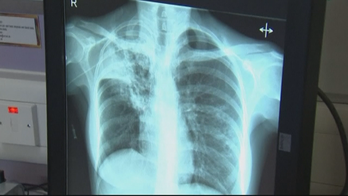

November 7, 2017 Minnesota county scrambles to control deadly tuberculosis outbreak A Minnesota county is grappling with the largest outbreak of tuberculosis in the country, as health officials count 17 confirmed cases including six fatalities.